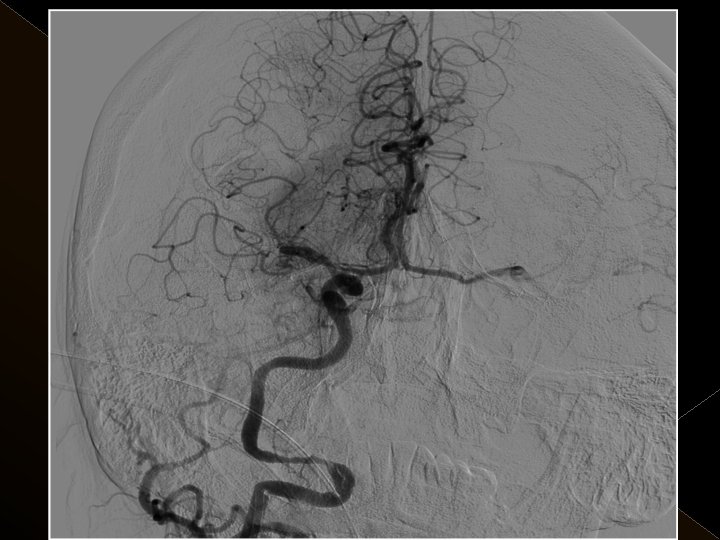

Acil servise başvuru süreleri: 1 -4. 5 saat Başvuru sırasındaki ortalama NIHSS skoru: 23 25 hastanın 21’inda kontrol serebral anjiografide tıkanıklığın tamamen açılmış olduğu görüldü. � Baziler arter ve ICA tıkanıklığı olan 4 hasta kaybedildi. � 19 hastanın 16’sında NIHSS skorlarında işlem sonrasında 24. saatte yapılan klinik değerlendirmede ortalama 10 puanlık düşüş saptandı. � � �

� İnme tedavisinde iv tpa uygulamasını takiben � intraarteriyel (İA) trombolitik tedavi (ia tpa ve ia mekanik trombolizis) � İA stent yardımı ile trombektomi yöntemleri kullanılarak tedaviye cevap ve komplikasyonlar araştırıldı.